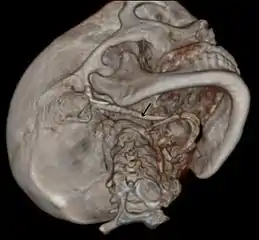

3D-reconstructed CT scan showing bilateral stylohyoid ligament ossification

3D reconstructed CT scan showing elongated styloid process (right side)